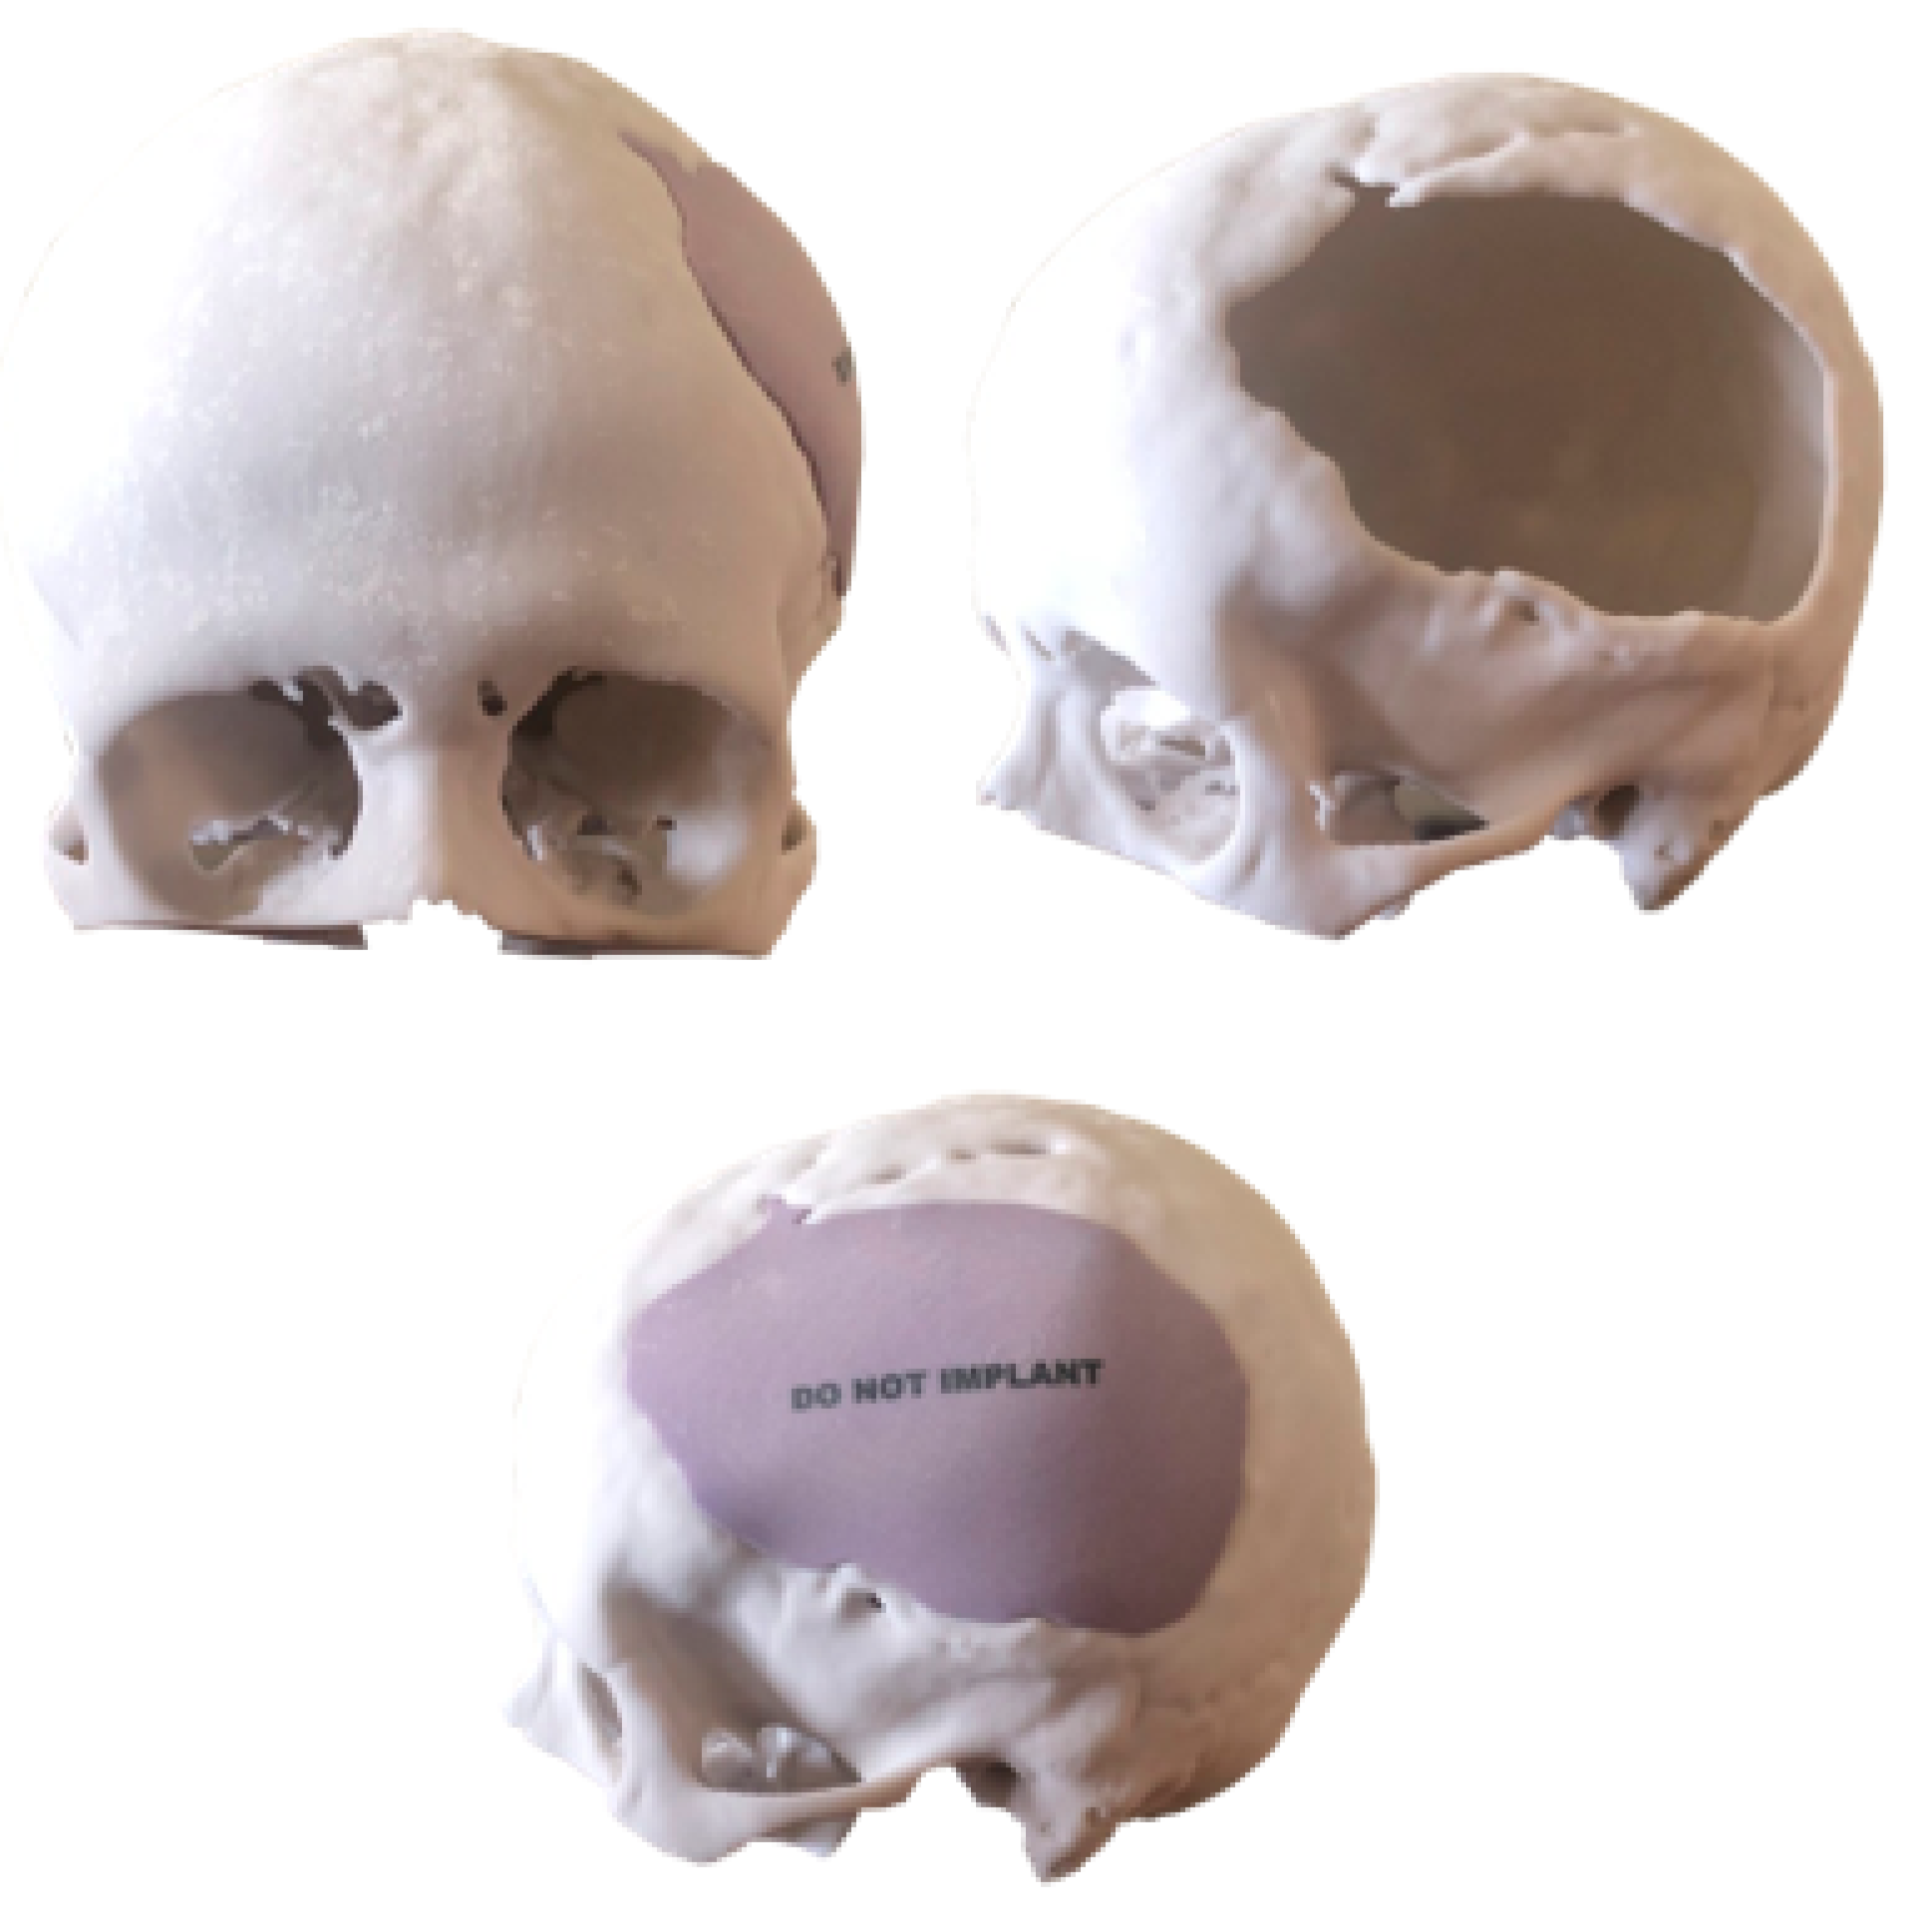

3.1.3. Planning and Printing Anatomical Model

3.2.3. Anatomical Model Printing

3.3.3. Planning and Printing Anatomical Models